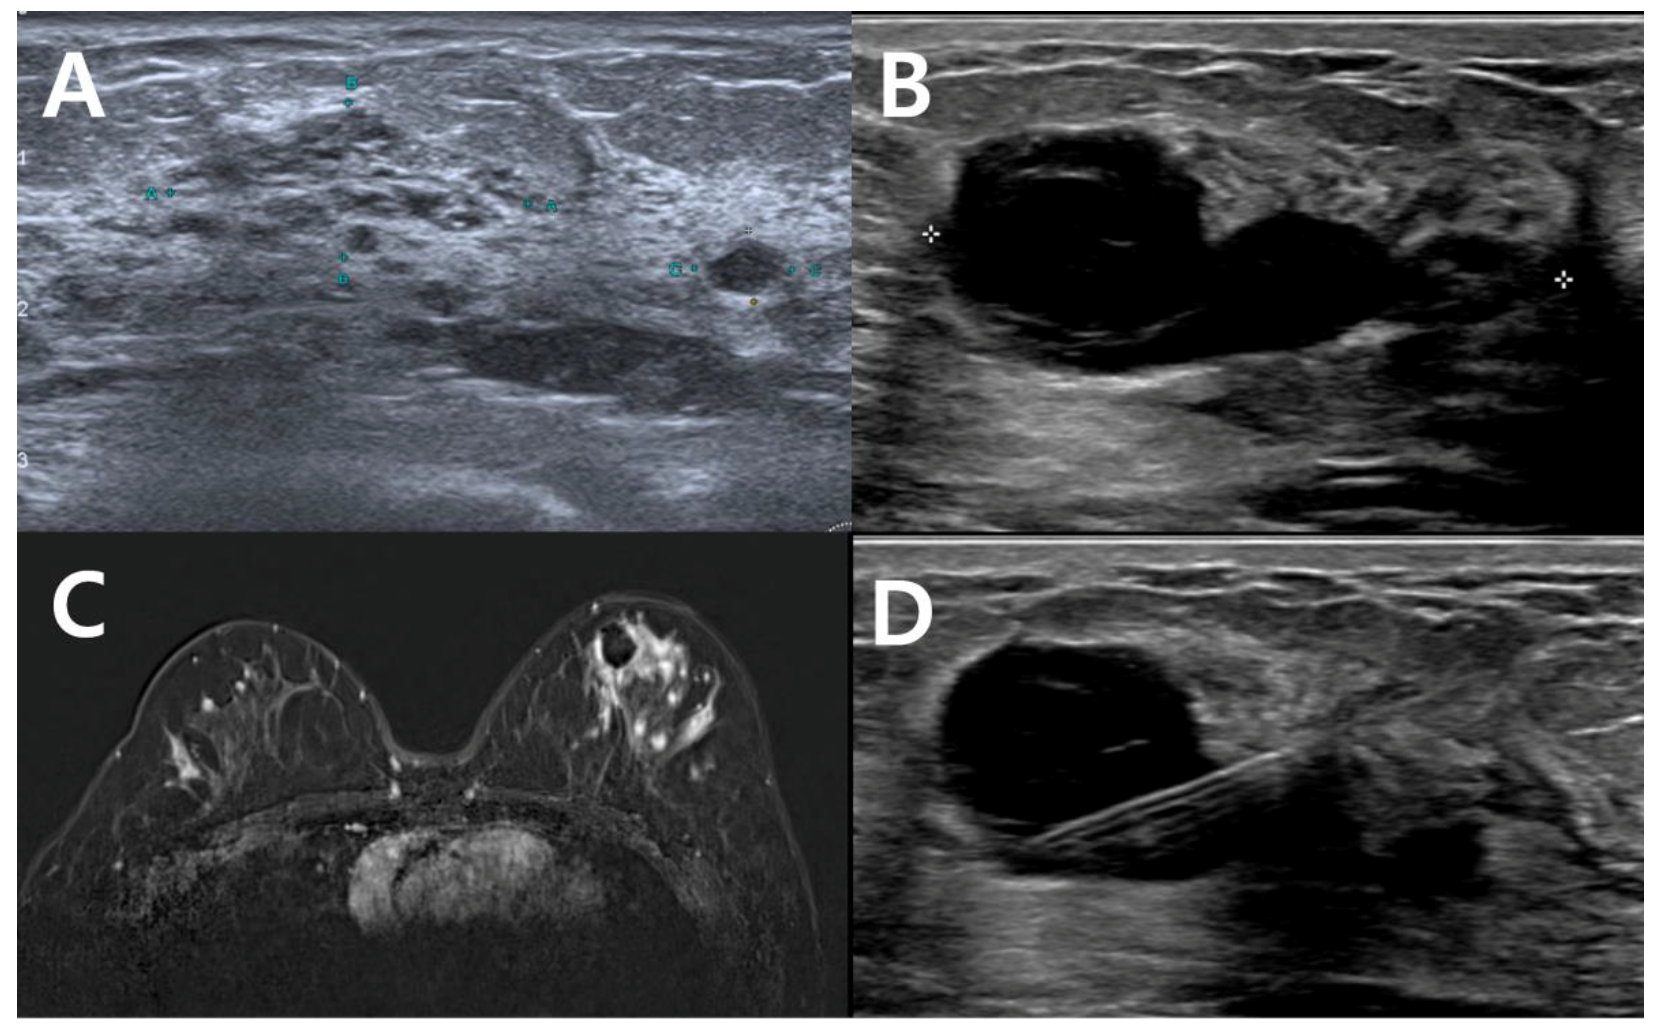

3.2. Diagnostic Performances of Imaging Modalities for Detecting Remnant Lesions

| Mammography (n = 26) | Ultrasonography (n = 47) | MRI (n = 49) | |

|---|---|---|---|

| Sensitivity | 5/23 (21.7%) | 22/38 (57.9%) | 24/40 (60.0%) |

| Specificity | 3/3 (100%) | 6/9 (66.7%) | 6/9 (66.7%) |

| PPV | 5/5 (100%) | 22/25 (88.0%) | 24/27 (88.9%) |

| NPV | 3/22 (13.6%) | 6/22 (27.2%) | 6/22 (27.2%) |

| Accuracy | 8/26 (30.8%) | 28/47 (59.6%) | 30/49 (61.2%) |